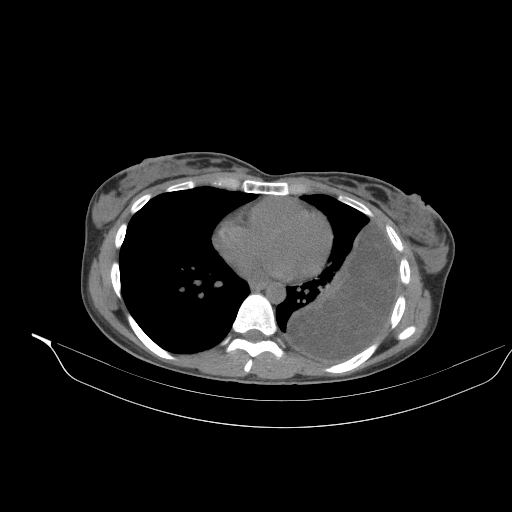

Nhiễm sán dải chó ở phổi (Pulmonary hydatid infection)